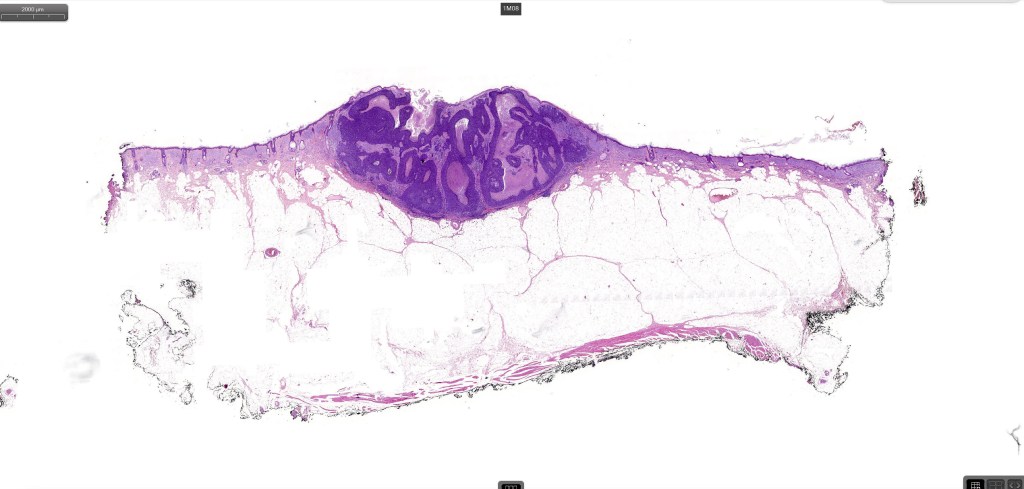

Histological features

•Both epithelial & fibrous stromal components

•The tumor commonly arises from the epidermis

•The epithelial component is composed of uniform small, basophilic devoid of desmosomes

•Peripheral palisading

•Retraction artifact with stromal mucin

•A wide variety of histological variants are possible including nodular, nodulocystic, ulcerative, superficial, micronodular, infiltrating/infiltrative, keratotic, basosquamous, pigmented, morpheaform, keloidal, clear-cell, signet-ring cell & granular cell variants, BCC with monster cells, BCC with metaplastic features, BCC with matricial differentiation, basomelanocytic tumor (see separate blog), BCC with thickened basement membrane, BCC with carcinoid-like nuclear palisading & these are illustrated below